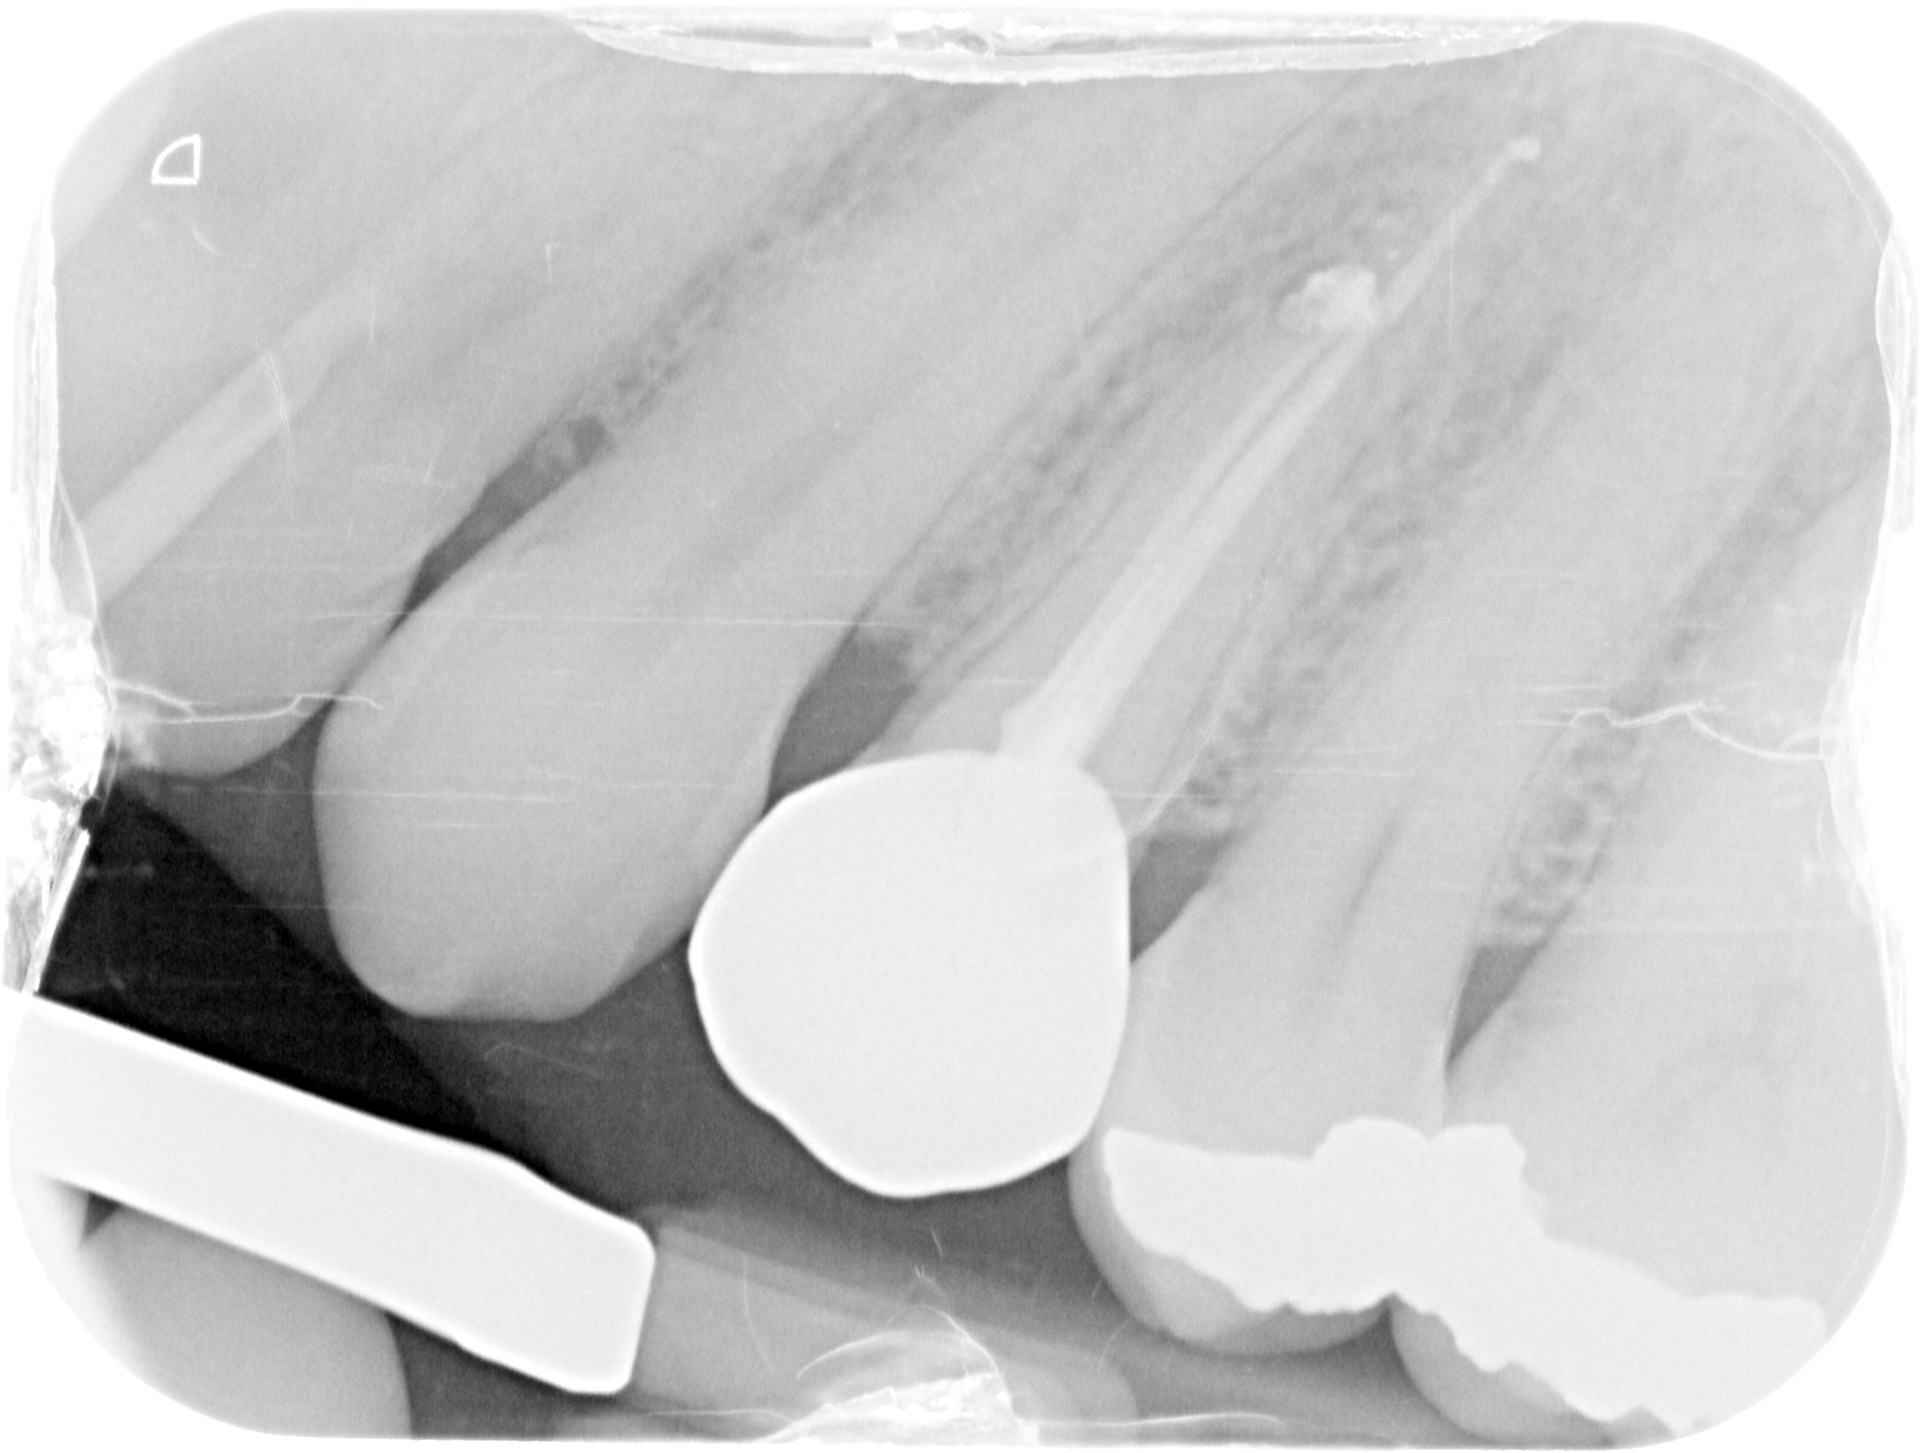

FINAL